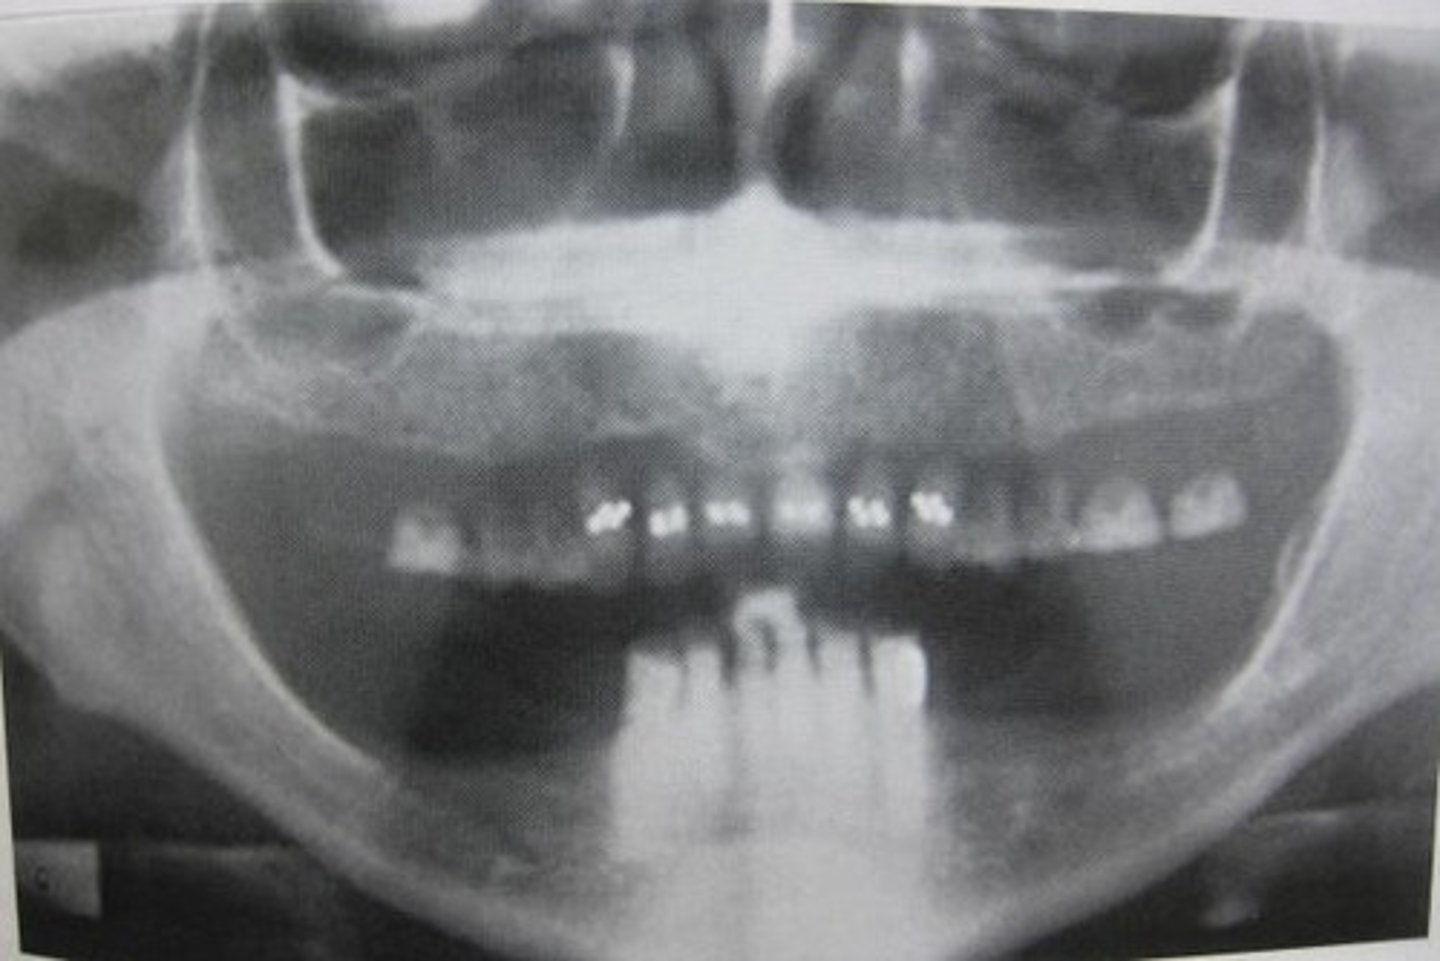

endosseous

placed within alveolar bone

based on concept of osseointegration

consists of 3 parts: fixture, abutment, prosthesis

subperiosteal

rests directly on bone under soft tissue

transosteal

horizontal support soft tissue

used for patients with atrophic mandible